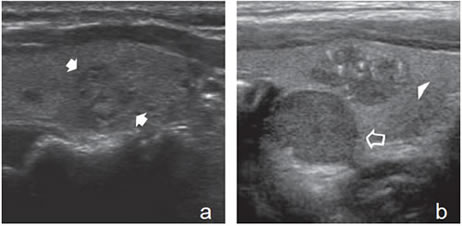

Un nódulo que tiene un componente quístico significativo, usualmente es un nódulo benigno hiperplástico, que ha acumulado abundante coloide (Figura 2a) o bien, un nódulo sólido que ha experimentado un proceso de degeneración colicuativa o hemorragia (Figura 2b). El coloide o el contenido líquido de un nódulo se ve anecogénico (negro en la imagen ecográfica) y las estructuras sólidas se ven ecogénicas (distintos tonos de grises), siendo la ecogenicidad similar al del parénquima tiroideo. En un nódulo sólido la ecoestructura y la ecogenicidad pueden ser variables. En general, la frecuencia de carcinoma es muy baja en nódulos quísticos13 y la mayoría de los carcinomas se presentan como nódulos sólidos (Figura 2c).

Figura 2. a) Quiste coloideo anecogénico y focos ecogénicos (flecha) con artefacto en cola de cometa; b) Nódulo mixto sólido-quístico (cabezas de flechas). Imagen vegetante (flecha) adherida a un tabique que se proyecta al lumen; c) Comparación entre el aspecto ecográfico de un cáncer papilar sólido (flecha abierta) y un quiste coloideo anecogénico.